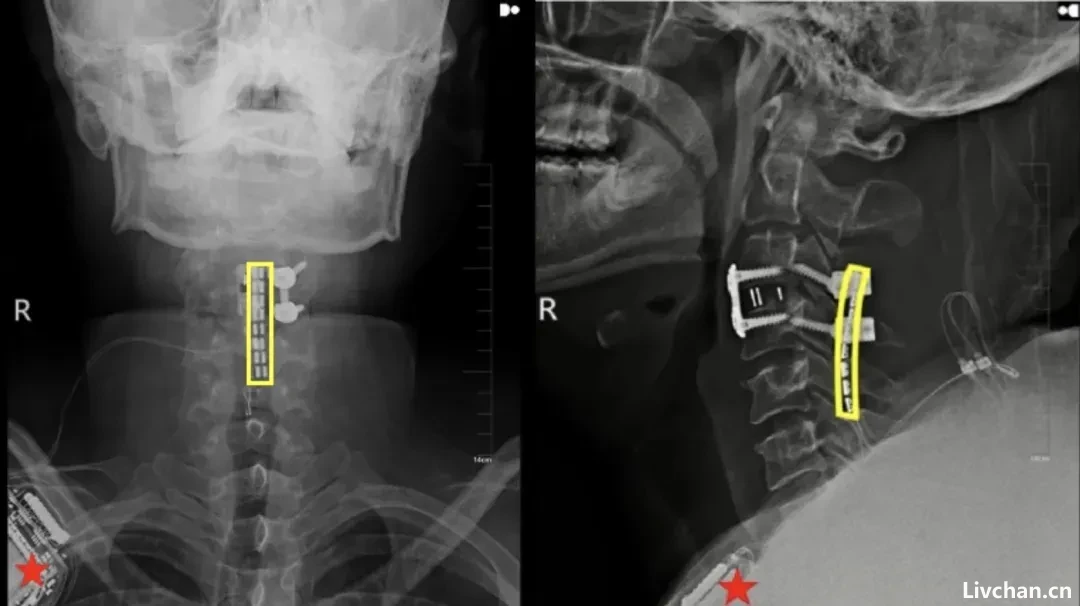

挽救生命是当务之急。刘先生入院后,吉大二院立即启动重伤救治绿色通道,由吴敏飞主刀完成神经减压内固定术。

值得一提的是,手术中,吴敏飞考虑到后续存在着脊髓神经接口植入的可能,同步在颈椎损伤段预留了一个“接口”。

手术非常成功,术后一个月,刘先生的恢复情况良好,生命体征保持稳定。但由于颈椎严重损伤致完全性截瘫,他的脖子以下彻底失去了运动能力和感觉,大小便失禁。